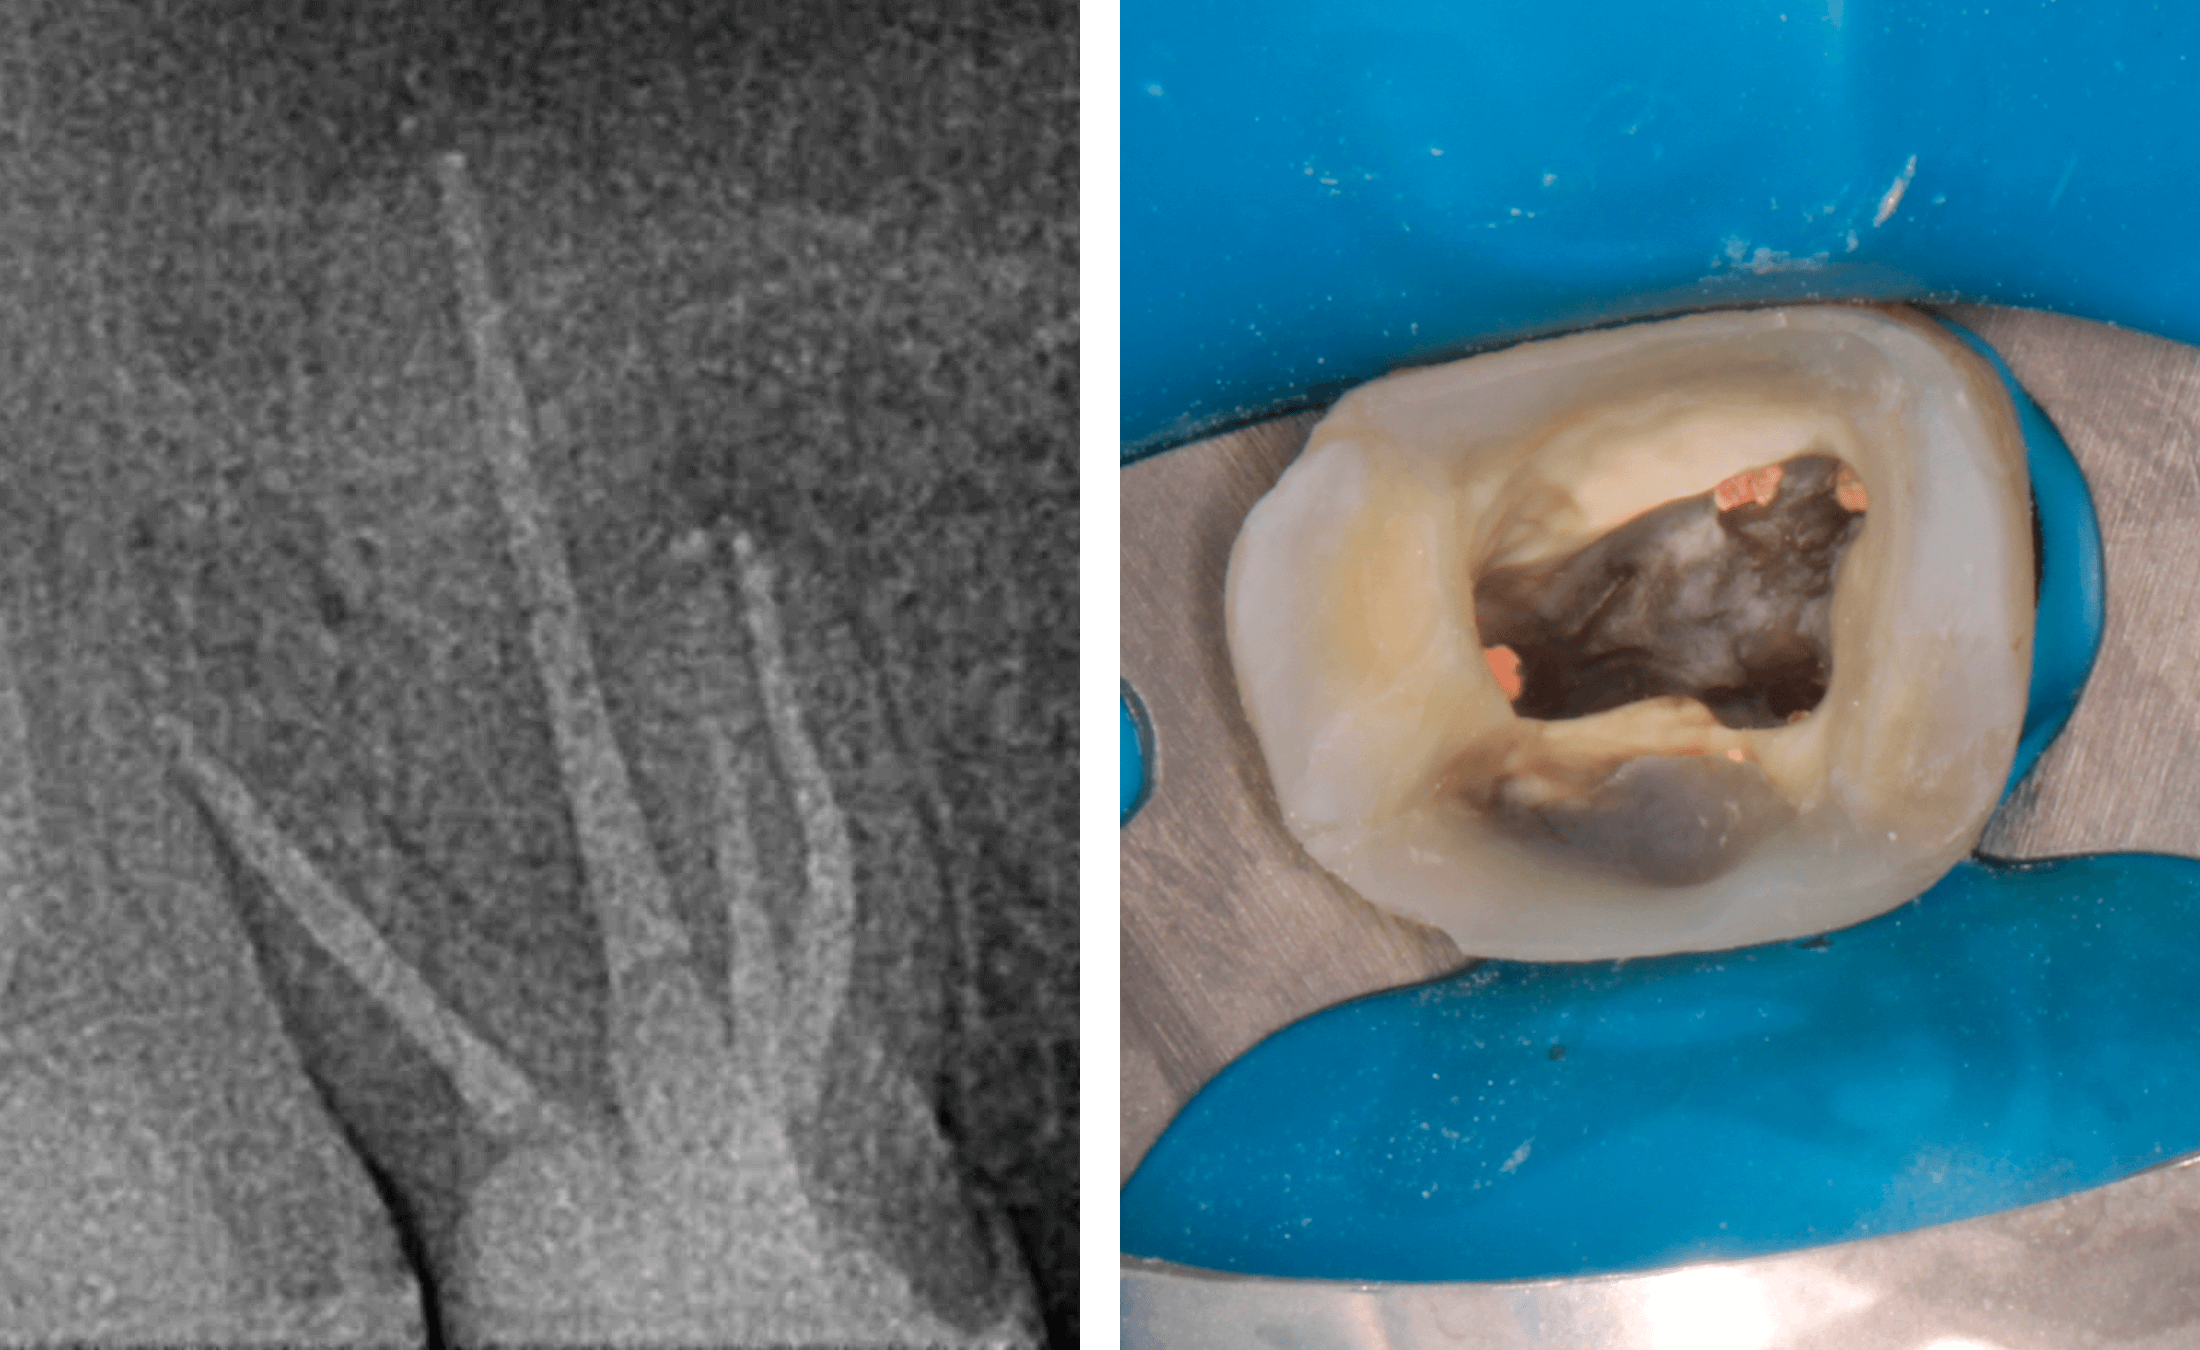

1. A case of tooth #16 presenting with chronic apical periodontitis featuring extensive mesiobuccal root periapical pathology (4-5mm lesion) and draining sinus tract, with evidence of prior incomplete endodontic treatment. (Image 1-4)

2. During the initial appointment, the following treatment was performed: complete revision of the root canal system, removal of existing obturation material, and thorough mechanical instrumentation combined with chemical disinfection. The canals were then temporarily obturated with a calcium hydroxide-based medication for a period of two weeks. (Image 5)